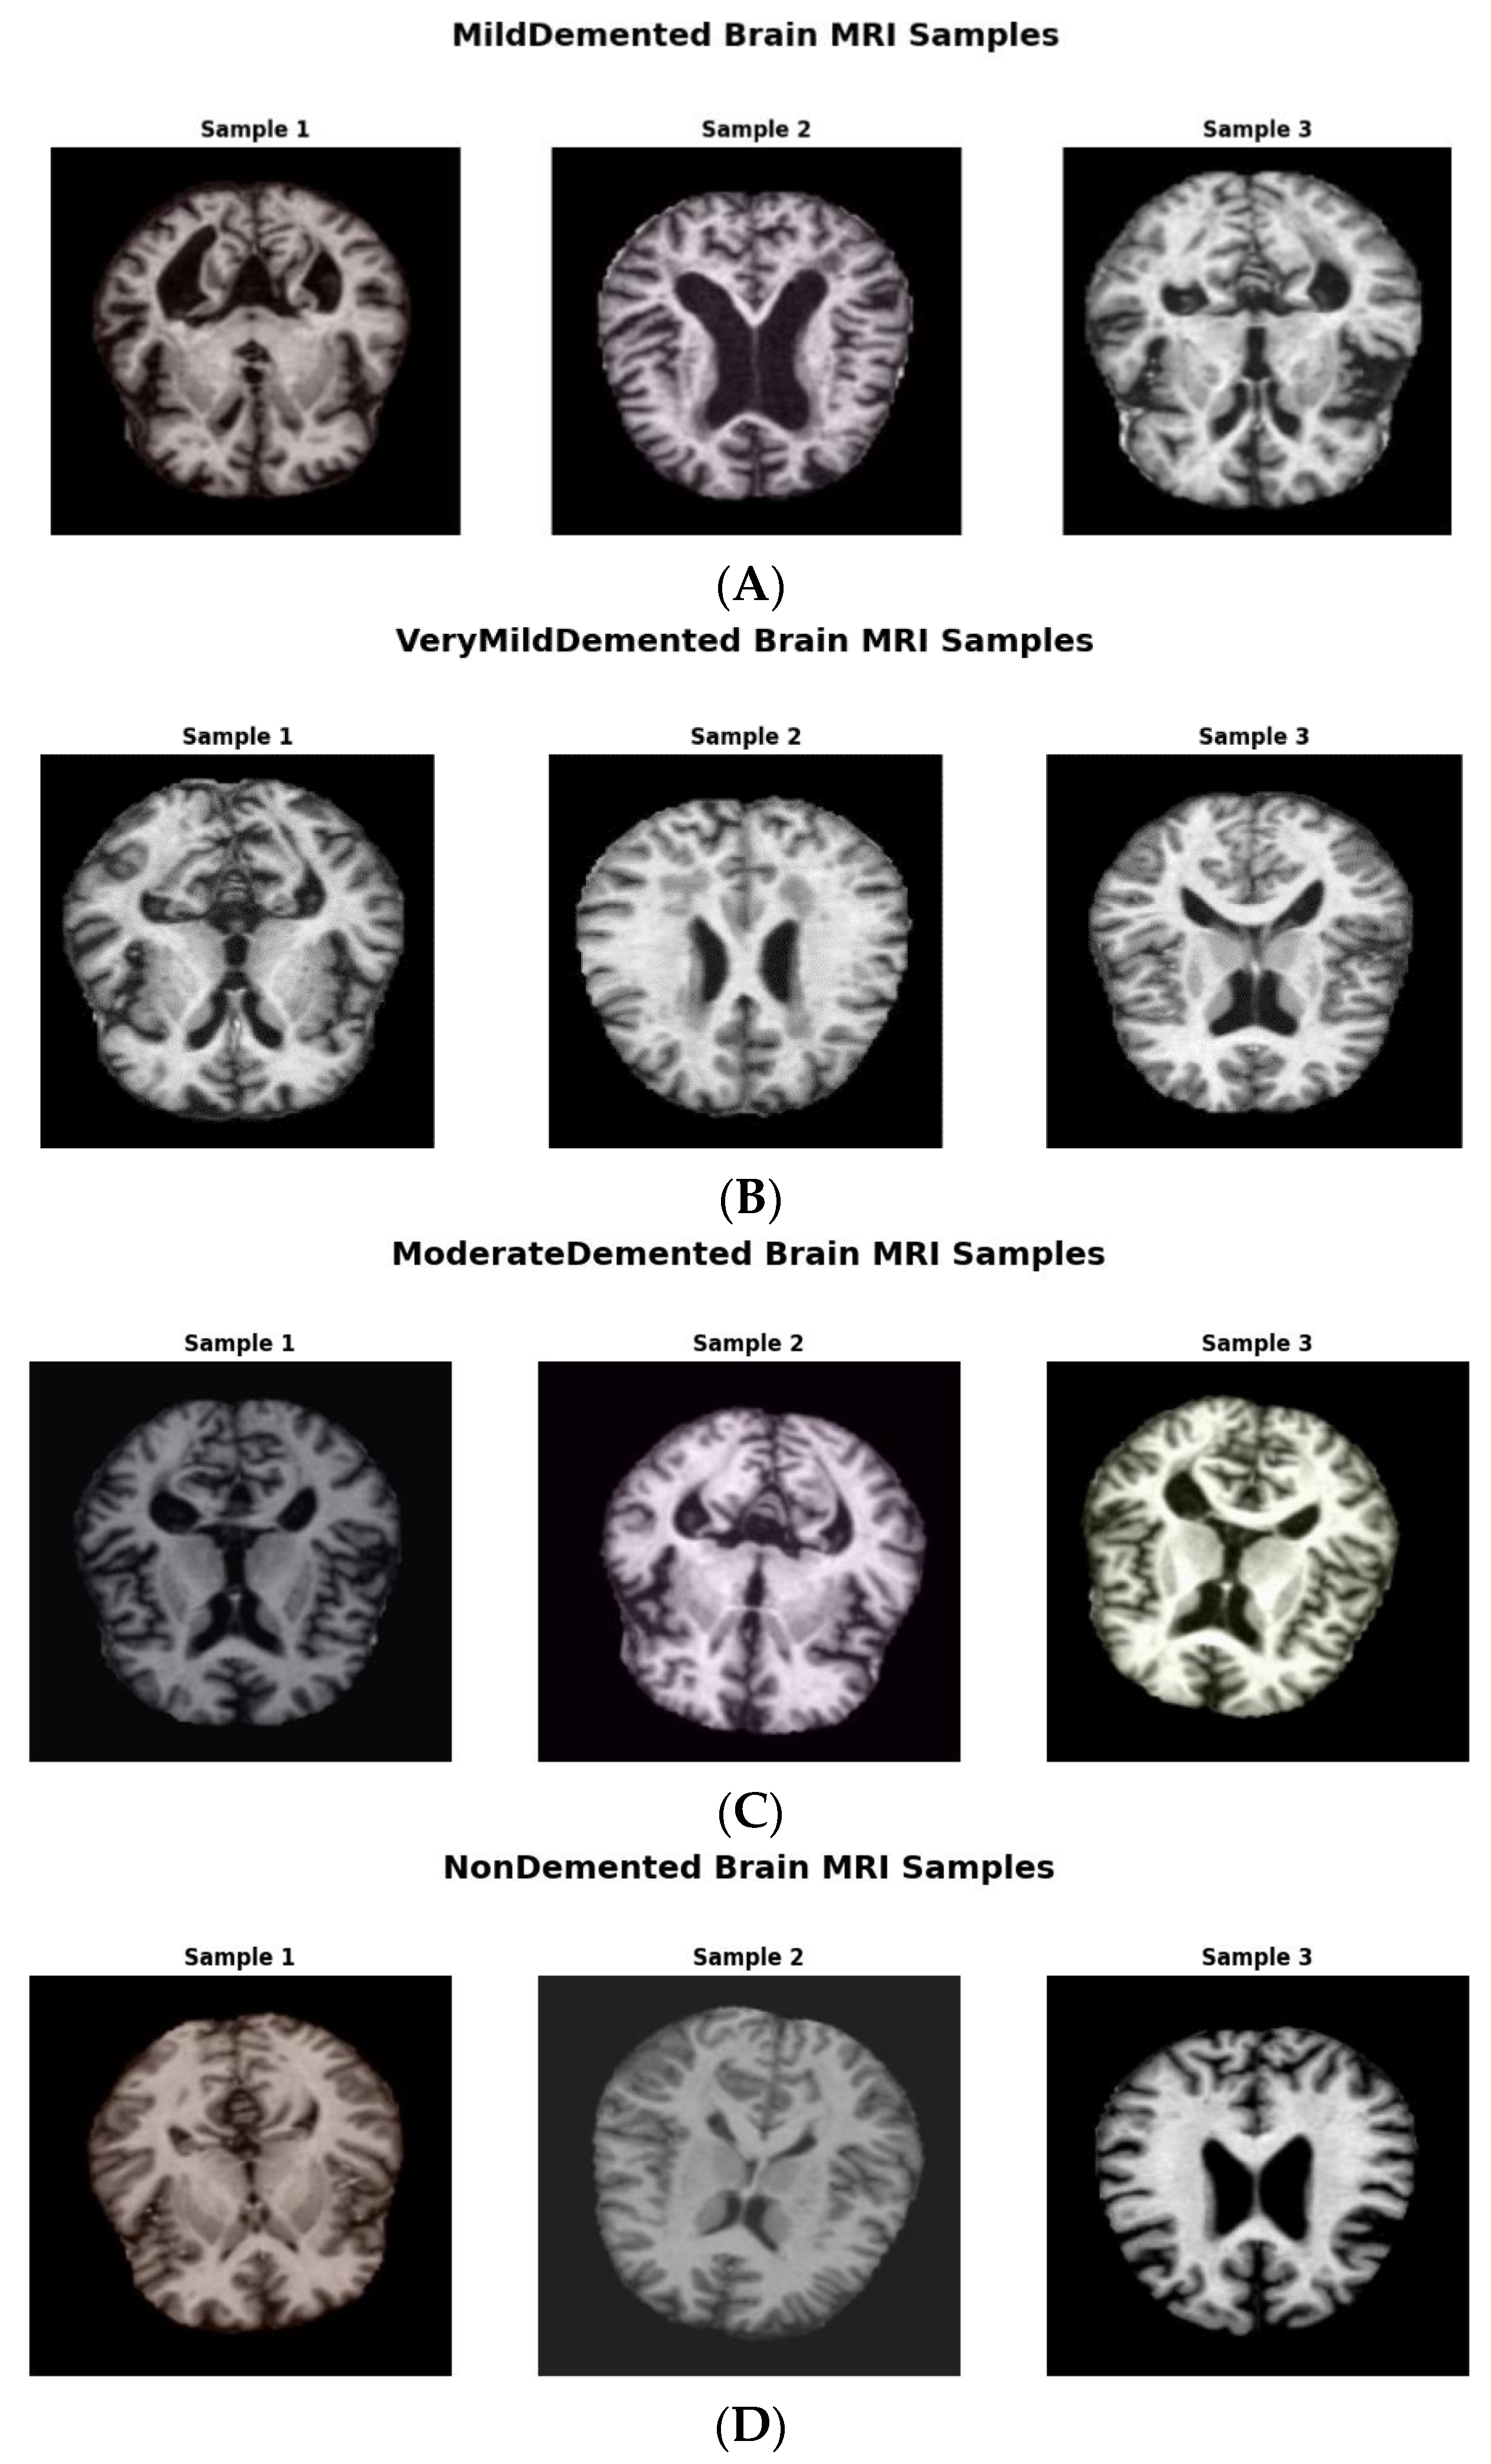

We obtained the initial AD dataset from the Kaggle website, available online: https:// www.kaggle.com/datasets/tourist55/alzheimers-dataset-4-class-of-images (accessed on 14 April 2024) [25]. It provides high-quality MRI scans organized into four classes representing distinct AD stages: VeryMildDemented, MildDemented, ModerateDemented, and NonDemented. Such structured categorization allowed us to take a multi-stage classification approach, as is required for early AD detection and progression monitoring [25]. Figure 1 shows image samples from each class, while Figure 2 shows augmented data samples and our implementation process to address class imbalances and issues with data homogeneity.

Figure 1. (A) MildDemented brain MRI samples. (B) VeryMildDemented brain MRI samples. (C) ModerateDemented brain MRI samples. (D) NonDemented brain MRI samples.